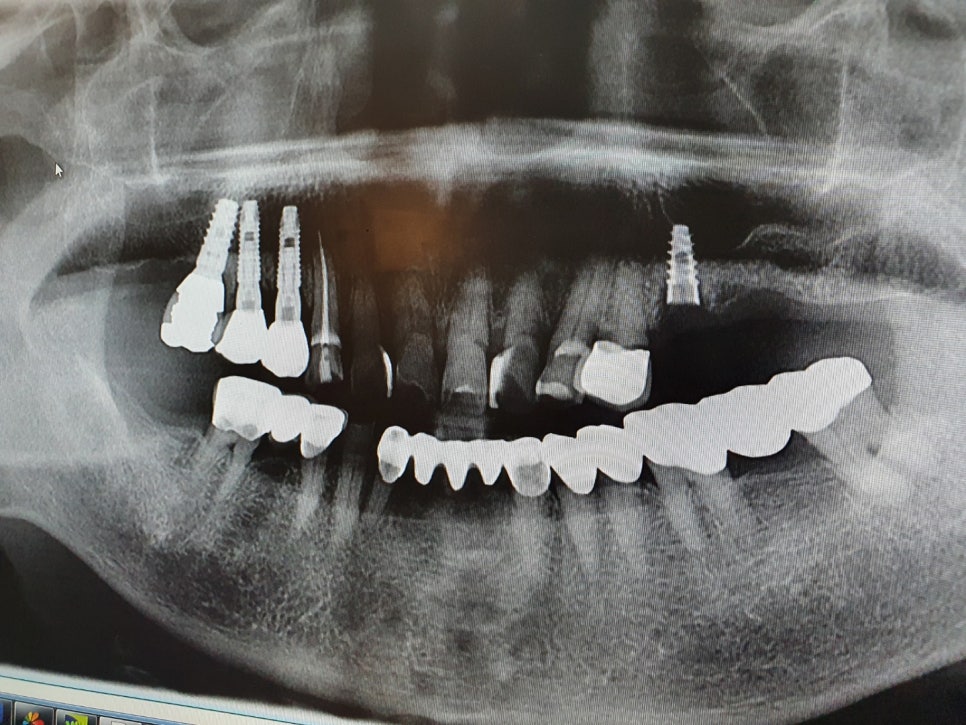

문진-파노라마촬영-ct촬영-임플란트식립-지대치연결-보철물연결

단순한임플란트과정은이렇습니다.

만약잇몸뼈가부실하다면 신논현역치과 임플란트 잘하는 스마일뷰치과에서는

임플란트식립전에 뼈이식을 진행하게 되는데

뼈이식비는임플란트비용에포함되지않습니다.